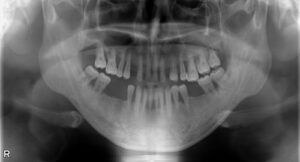

インプラント治療を成功させるうえで重要なのは、精密な治療計画です。そのためには顎の骨の状態を精密に把握する必要があります。そこで活躍するのが歯科用CTです。これまでのレントゲン検査とはくらべものにならないほどの詳細な情報を立体画像で確認することができます。

顎の骨の骨密度や厚み、さらに神経や血管の位置まで把握できるので、どの位置にどの角度でどれくらいの深さにどの種類のインプラントを埋入すればいいのかの綿密なシミュレーションが可能です。